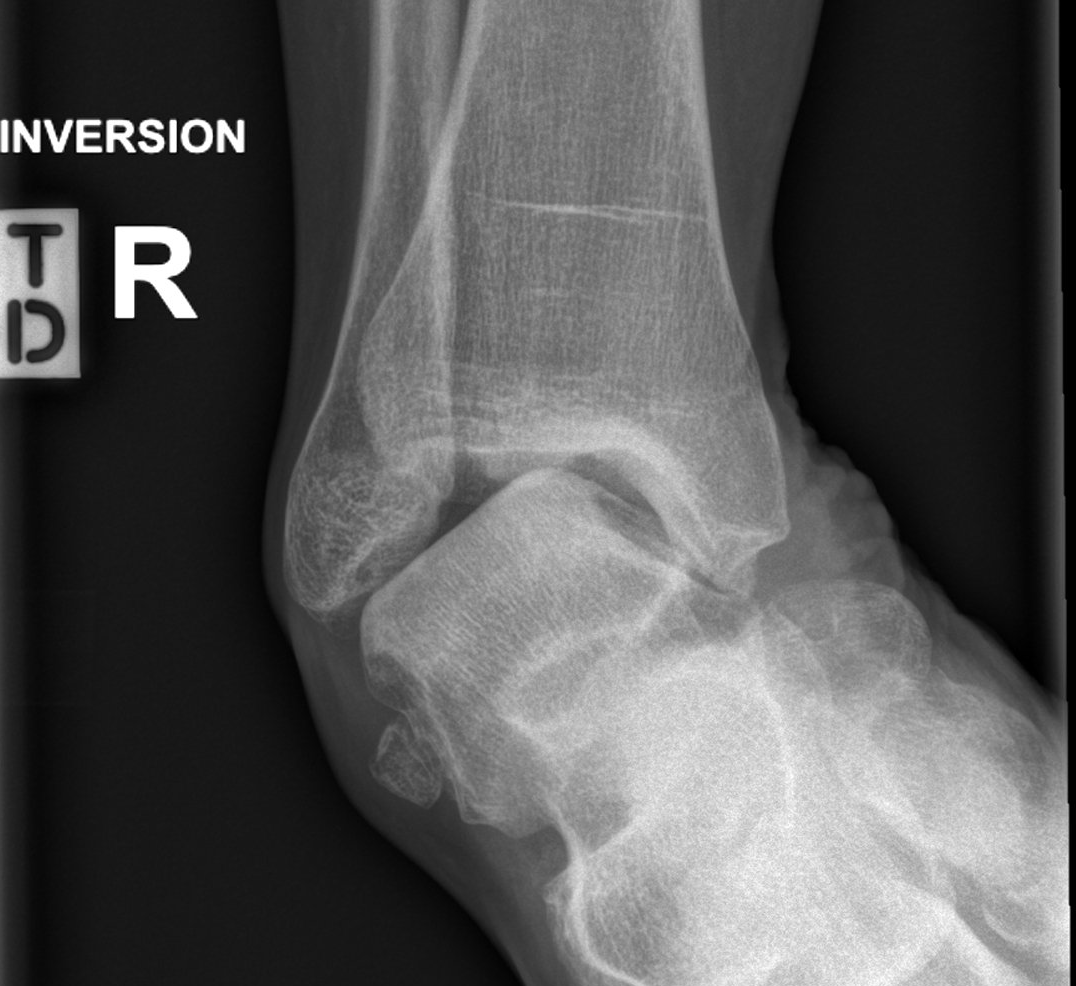

- ankle instability (see image below)

- weight-bearing X-rays of the ankle and foot